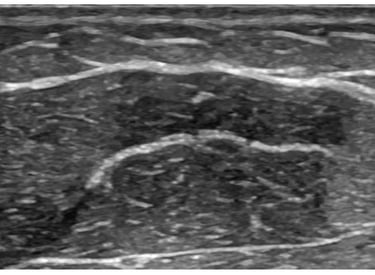

Ultrassom Intraoperatório

O ultrassom intraoperatório permite mapear estruturas e avaliar a espessura da gordura em tempo real, aumentando a precisão da lipoaspiração e a segurança do procedimento. Uma tecnologia essencial para resultados refinados e personalizados.